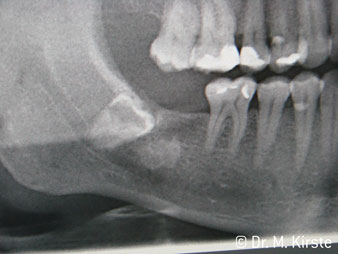

The 45° angle of the handpiece has been specially selected for its wide range of advantages. Colleagues who work in surgery, and for whom this handpiece was primarily developed, will soon appreciate the ability to work efficiently in very restricted spaces. In wisdom tooth extractions in particular (fig. 2) there is no need for large-scale spreading of the soft tissues in the cheek region (fig. 3). The design of the handpiece head combined with turning the head slightly during preparation allows work to be carried out quickly and safely in the retromolar region.

Fig. 2